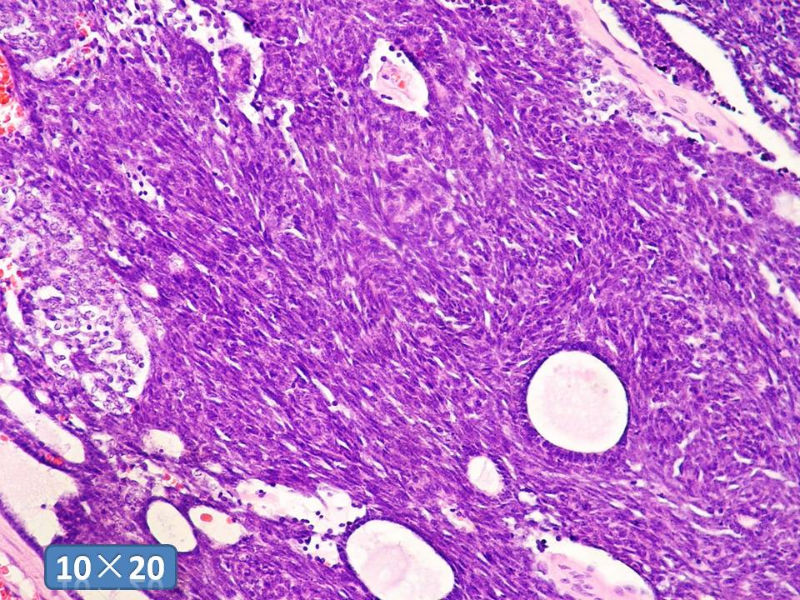

男性,49岁,间断左鼻腔出血3个月。

标签:是嗅母么?

1)嗅神经母细胞瘤?

2)腺肌上皮癌?

3)肌上皮癌?

4)神经内分泌癌?

5)腺样囊性癌?

6)其他?

腺肌上皮癌

感觉要排除畸胎癌肉瘤。

间质为恶性梭形细胞成分,其间感觉是腺体,两种成分密切相关....

免疫组化S-100的阳性区域方式...嗅母可能性大。

支持嗅神经母细胞瘤(伴有腺体分化)

嗅神经母细胞瘤

有上皮和间叶2种结构,畸胎性癌肉瘤是要考虑一下的吧!